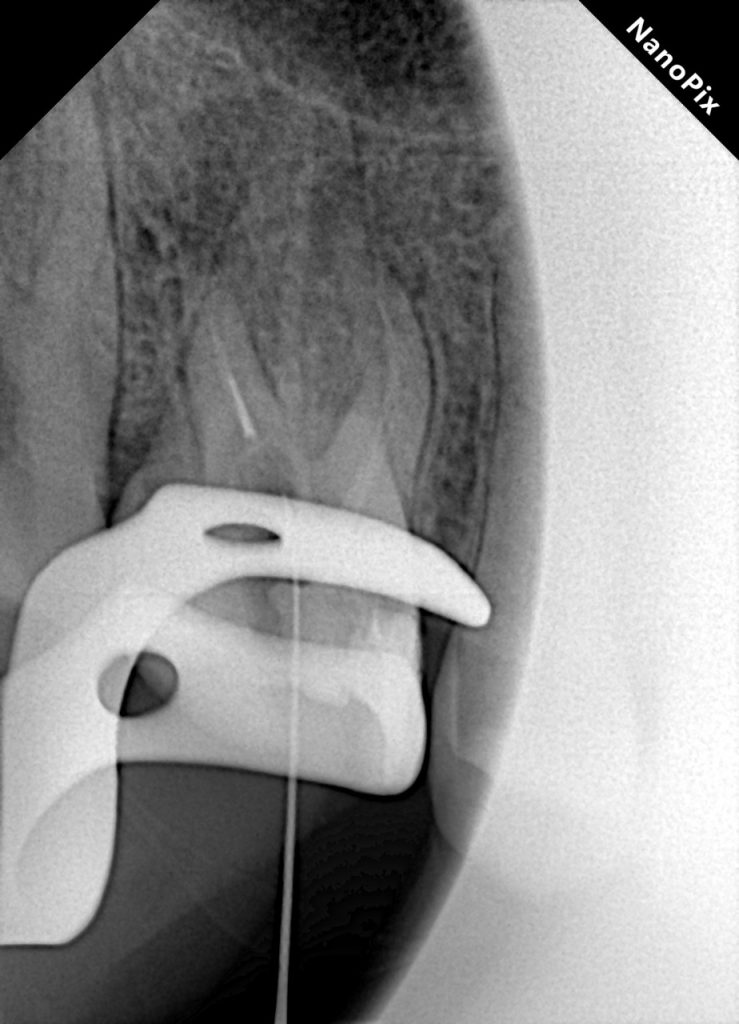

Using ultrasonic tips (ET20 & Start-X #3) under the microscope, dentin around the coronal aspect of the fragment was trough-shaped. The fragment was loosened by micro-vibration and retrieved using a fine micro-tweezer under magnification (Fig 2–3). Post-retrieval confirmation radiograph showed a clear distal path.

Fig 2–3: Ultrasonic troughing and fragment retrieval from distal canal.